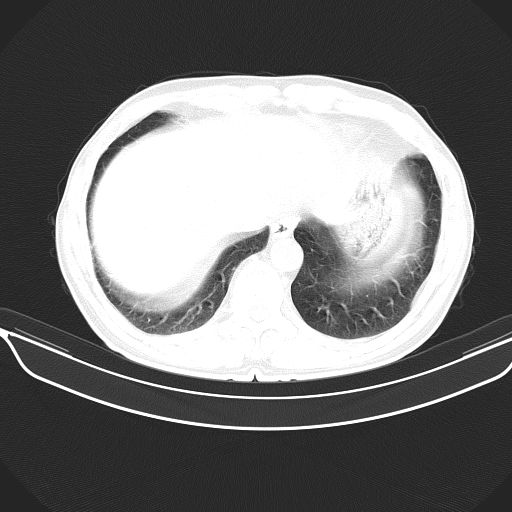

以下是引用shuiyuan在2010-3-1 10:45:00的发言:[br]考虑左肺上叶中心型肺癌伴阻塞型炎症,邻近胸膜受侵。

以下是引用心路寻觅在2010-3-1 10:23:00的发言:[br]1、考虑左肺上叶周围型肺癌[br]2、右上肺陈旧性病灶。[br][br][本贴已被 心路寻觅 于 2010-3-1 10:40:18 修改过]